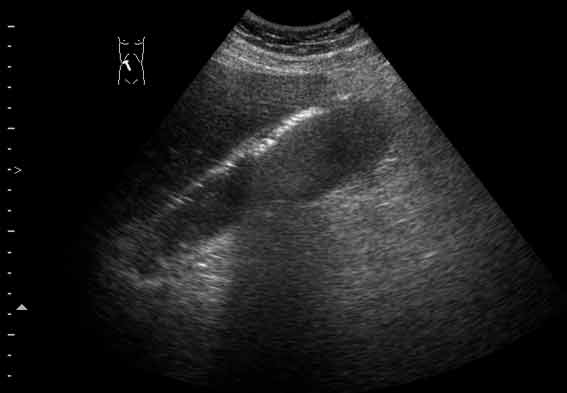

Острый эмфизематозный холецистит

Острый эмфизематозный холецистит. В желчном пузыре определяется газ, он располагается при малейшем изменении положения тела в самой верхней точке желчного пузыря. Газ в пузыре (СО2) является продуктом жизнедеятельности бактерий и при отсутствии ятрогенных вмешательств чаще всего указывает на эмфизематозное воспаление.